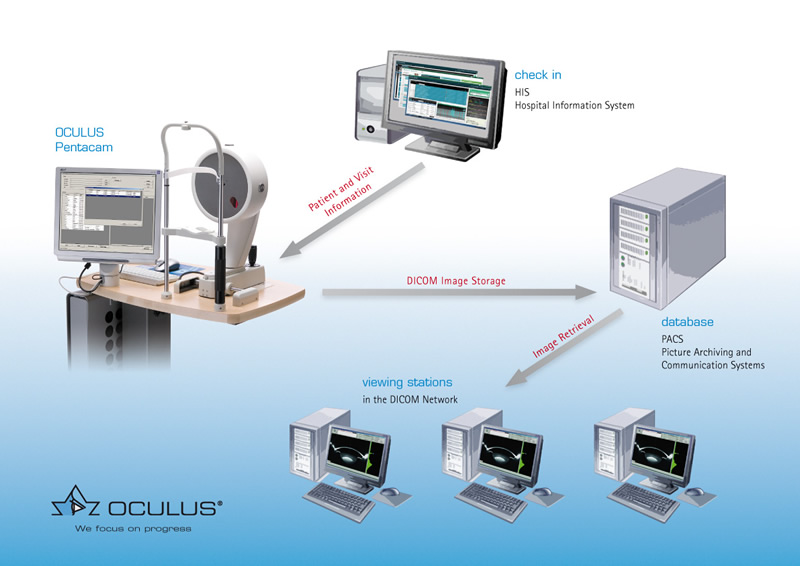

Лазерная камера для печати медицинских изображений на пленке стандарт dicom